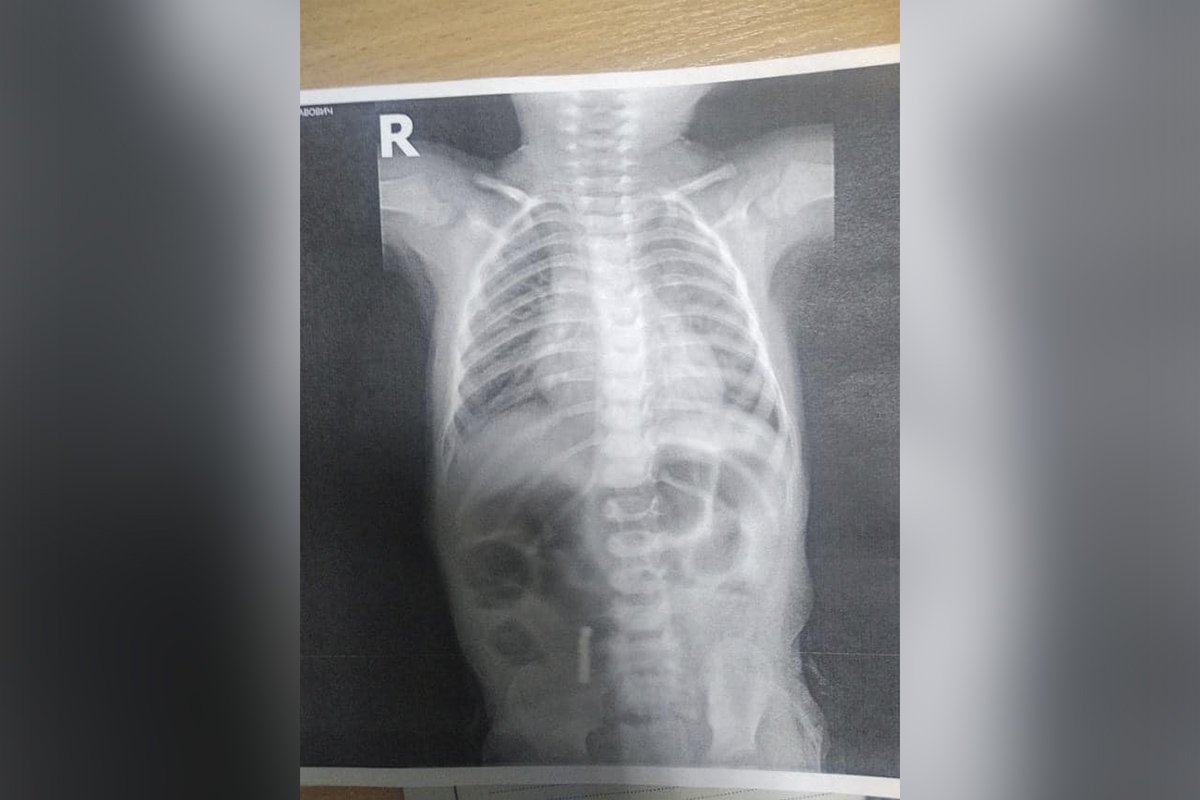

Малыша сразу отправили на операцию в отделении неотложной хирургической помощи. Несколько часов две команды хирургов и эндоскопистов извлекали посторонние предметы из кишечника мальчика.

«Сложность оперативного лечения заключалась в том, что шесть магнитов находились на разных уровнях желудочно-кишечного тракта: в тонком кишечнике и в просвете двенадцатиперстной кишки. Большей беды, слипания стенок кишечника, удалось избежать. Однако 5 дней, проведенных с малышом в реанимации, мама с папой запомнят на всю жизнь: оперативное вмешательство пытались провести с максимальной минимизацией рисков для пациента, но маленькие детали успели продырявить кишечник, а некоторые пораженные участки вообще почернели – такова сила сжатия этих магнитов», - сообщили в больнице.